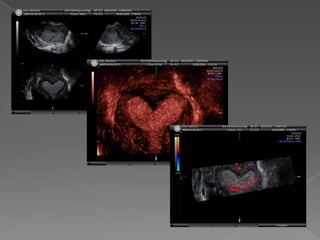

 El barridode la zona de interés  Obtención de un volumen de  Información  Representación y navegación en los tres planos ortogonales espaciales.  Evaluación de la forma de la cavidad uterina  Las imágenes pueden observarse en una orientación distinta a la de la adquisición del volumen .

• 16.

 Información puede enviarse por Internet  Re-escaneo del volumen , solicitar segunda opinión  Diagnóstico de malformaciones de forma no invasiva.  Evaluación de la forma externa del útero.  Visión de la cavidad endometrial en el corte